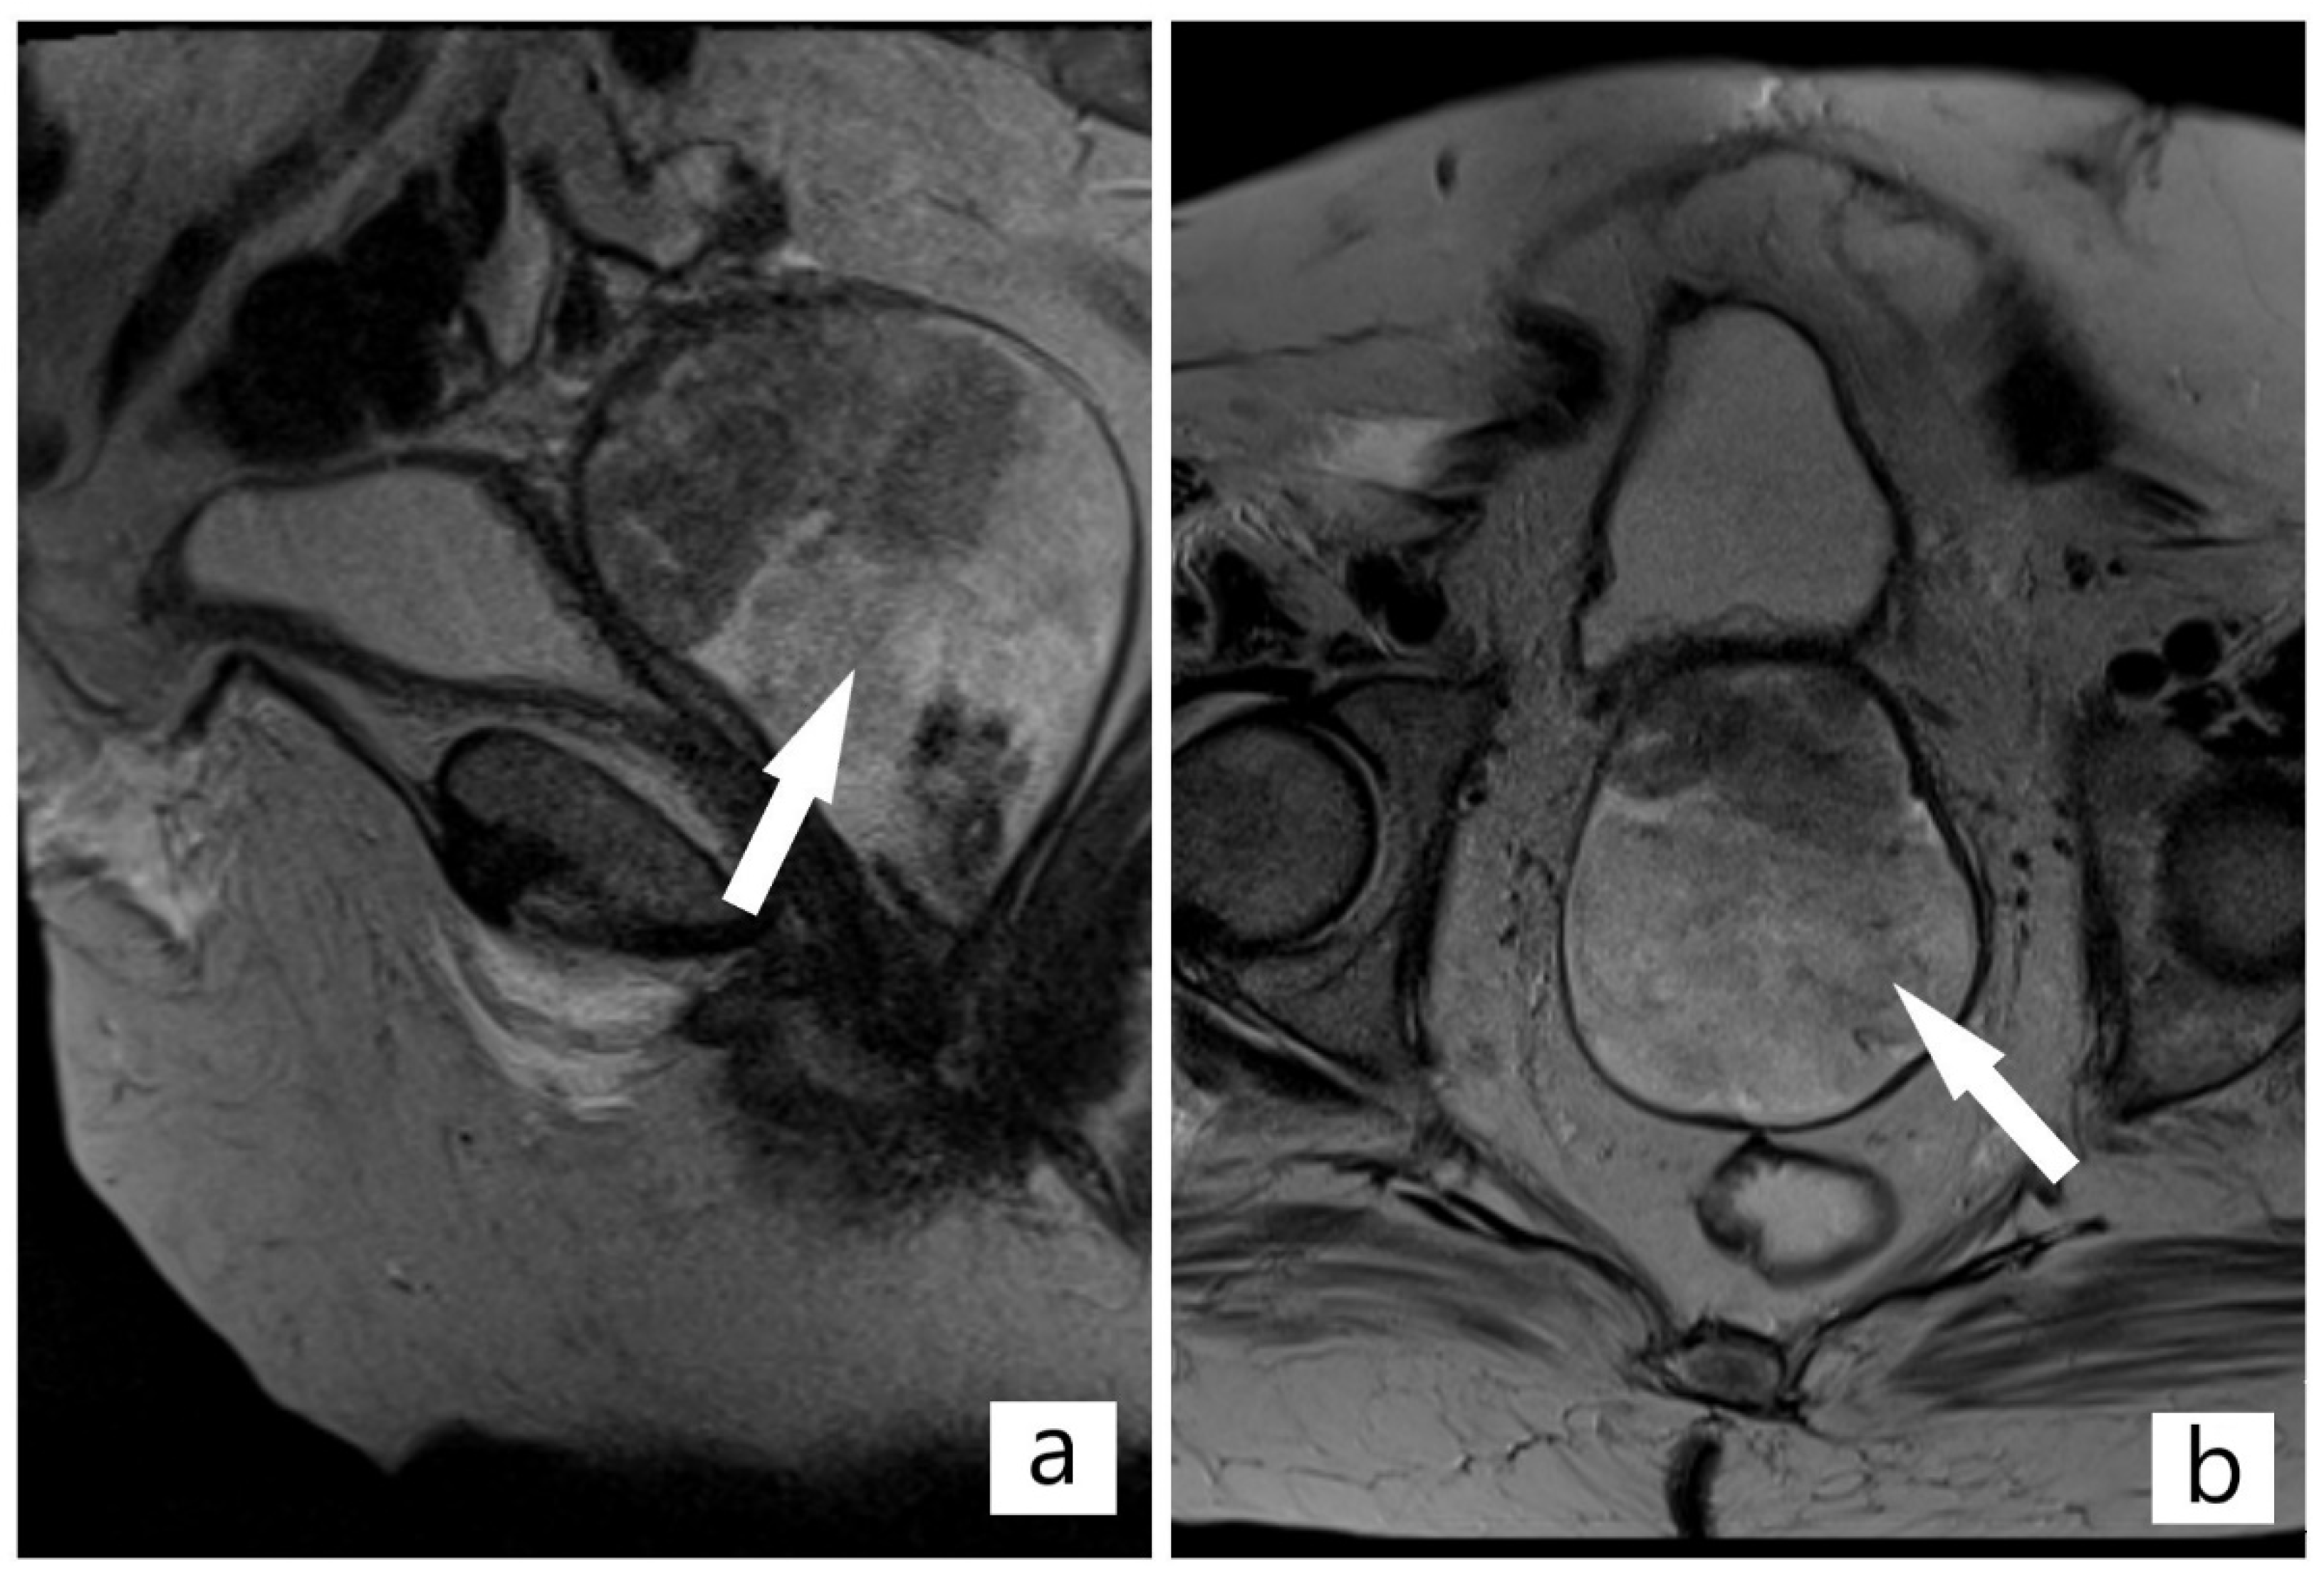

2. Case Presentation